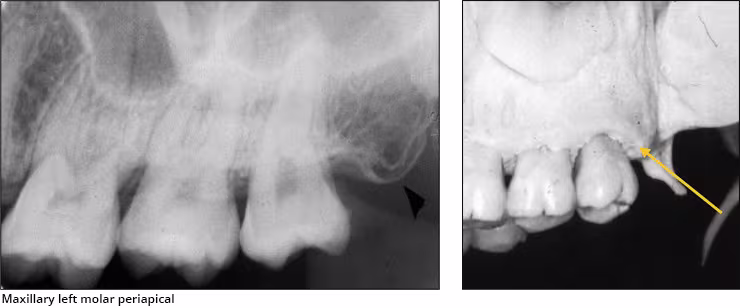

Pterygoid plates – The lateral and medial pterygoid plates are located behind the maxillary tuberosity. They project a single image configured like a thin wing of bone extending posteriorly from the tuberosity. This bilateral radiopacity is occasionally recorded on maxillary molar periapical images when the receptor is positioned adequately posterior.

Hamular process – The hamular process or pterygoid hamulus is a tiny finger or hook-like projection of bone that extends inferiorly from the medial pterygoid plate. This bilateral radiopacity occasionally appears on maxillary molar periapical images and molar bitewings when the receptor is positioned sufficiently posterior to record it.